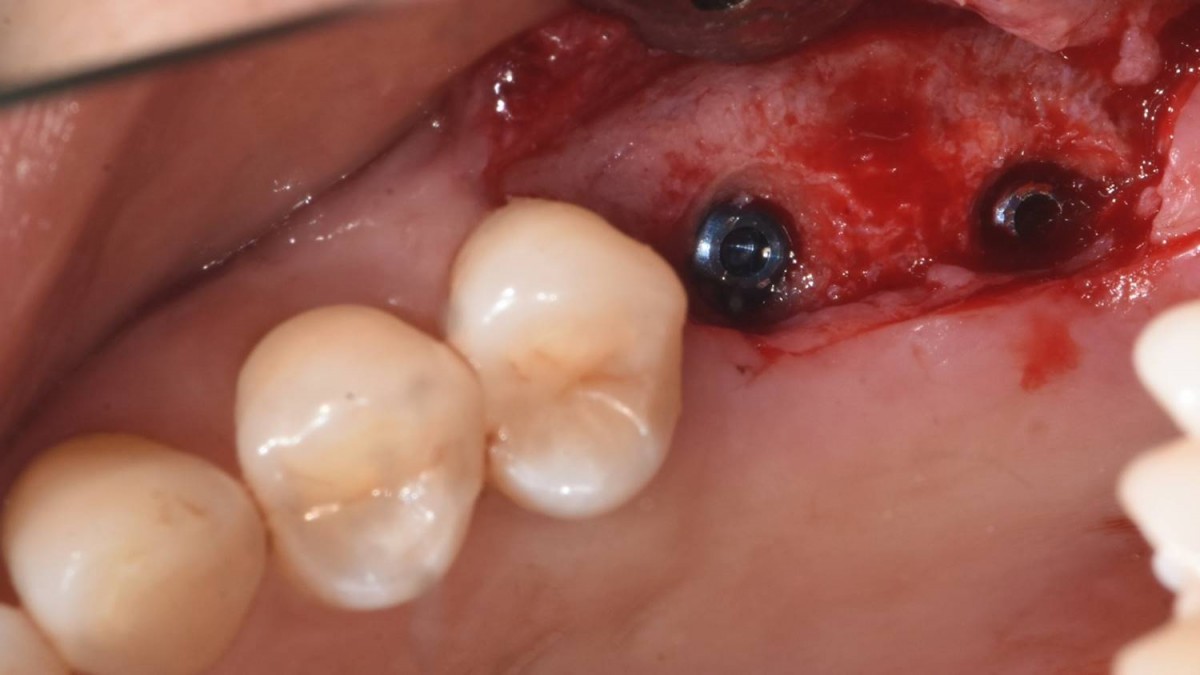

Implant in the molar zone of both jaws

A 55-year-old female patient had

bilateral problems in both jaws.

It was decided to proceed with implant-supported restoration in the left molar part first.